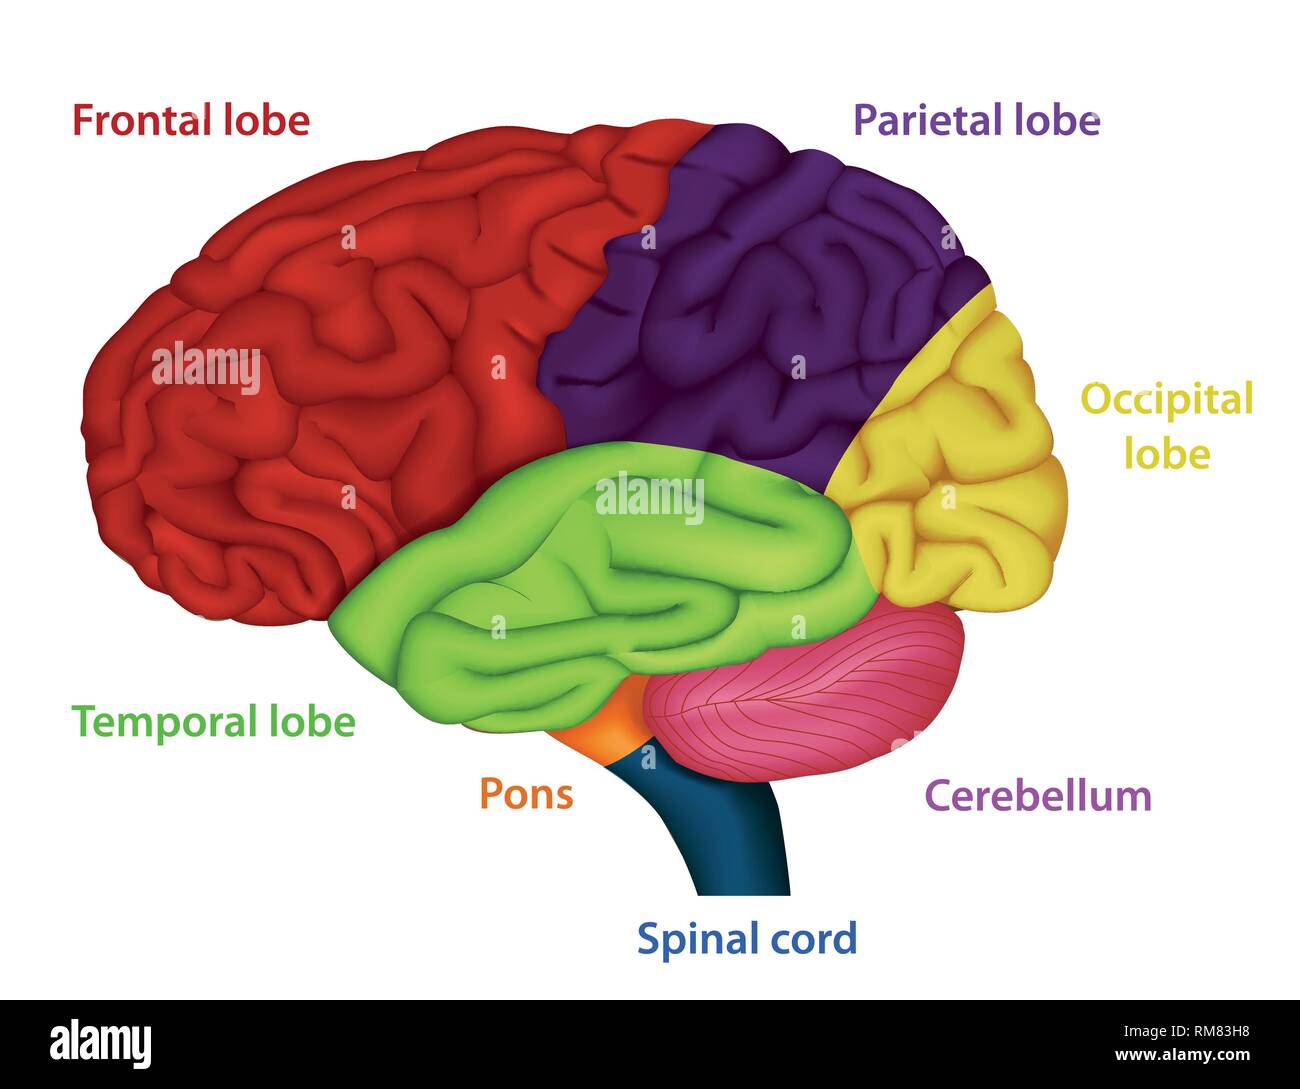

RF2R1KGAT–Struttura cerebrale umana. Emisferi e lobi della corteccia cerebrale. lobi frontali, temporali, occipitali e parietali. vista laterale e superiore

RF2Y8XEWG–Anatomia del cervello umano. Emisferi cerebrali, corteccia cerebrale, frontale, parietale, temporale, lobi occipitali, cervelletto e tronco cerebrale, fessura cerebrale.

RF2E374NN–Struttura dell'illustrazione della corteccia cerebrale. Regioni anatomiche colorate responsabili dell'intelligenza e del movimento.

RFTWMKBD–Aree funzionali del cervello umano. Assegnazione di aree in vista laterale del cervello. Illustrazione Vettoriale

RF3BJ1K42–Anatomia del cervello umano. Lobi frontali, occipitali, parietali e temporali, cervelletto e tronco cerebrale. Poster dettagliato del vettore